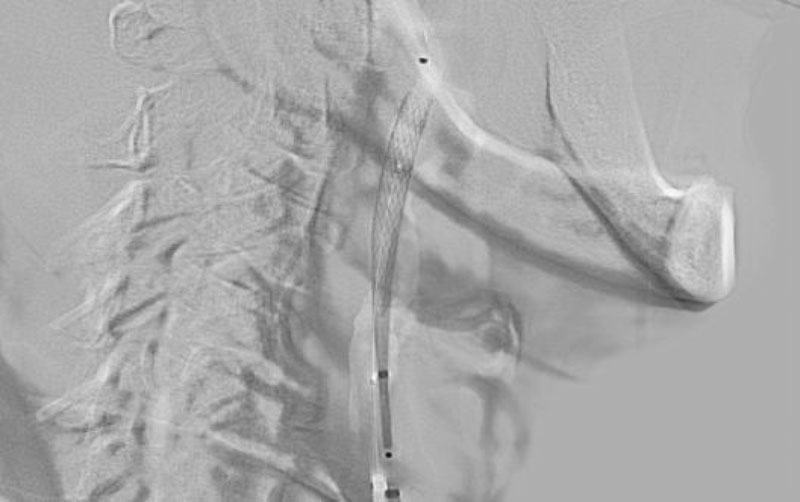

1313

'22年11月22日

右頚部内頚動脈狭窄症

70代

大阪府の病院

手術写真

治療

前

中

後

手術日